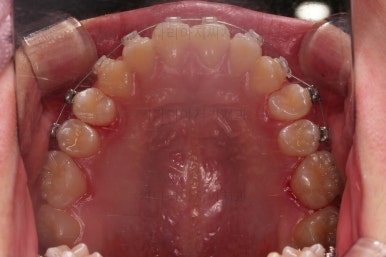

동래교정치과 초진 시 입안의 모습입니다.

치아가 벌어진 것도 벌어진 것이지만 교합이 전혀 안되고 있었어요.

틈새도 아랫니에 훨씬 많았고요.

윗니가 있는 위턱뼈가 전반적으로 아래턱에 비해 3차원으로 작은 양상이었습니다.

이번 환자분은 아랫니가 전반적으로 앞이든, 뒤든, 양옆으로든 넓어져 있는 양상이었고 그래서 아랫니에 틈도 많고 아래 앞니도 밀려나와 있는 양상인거죠.